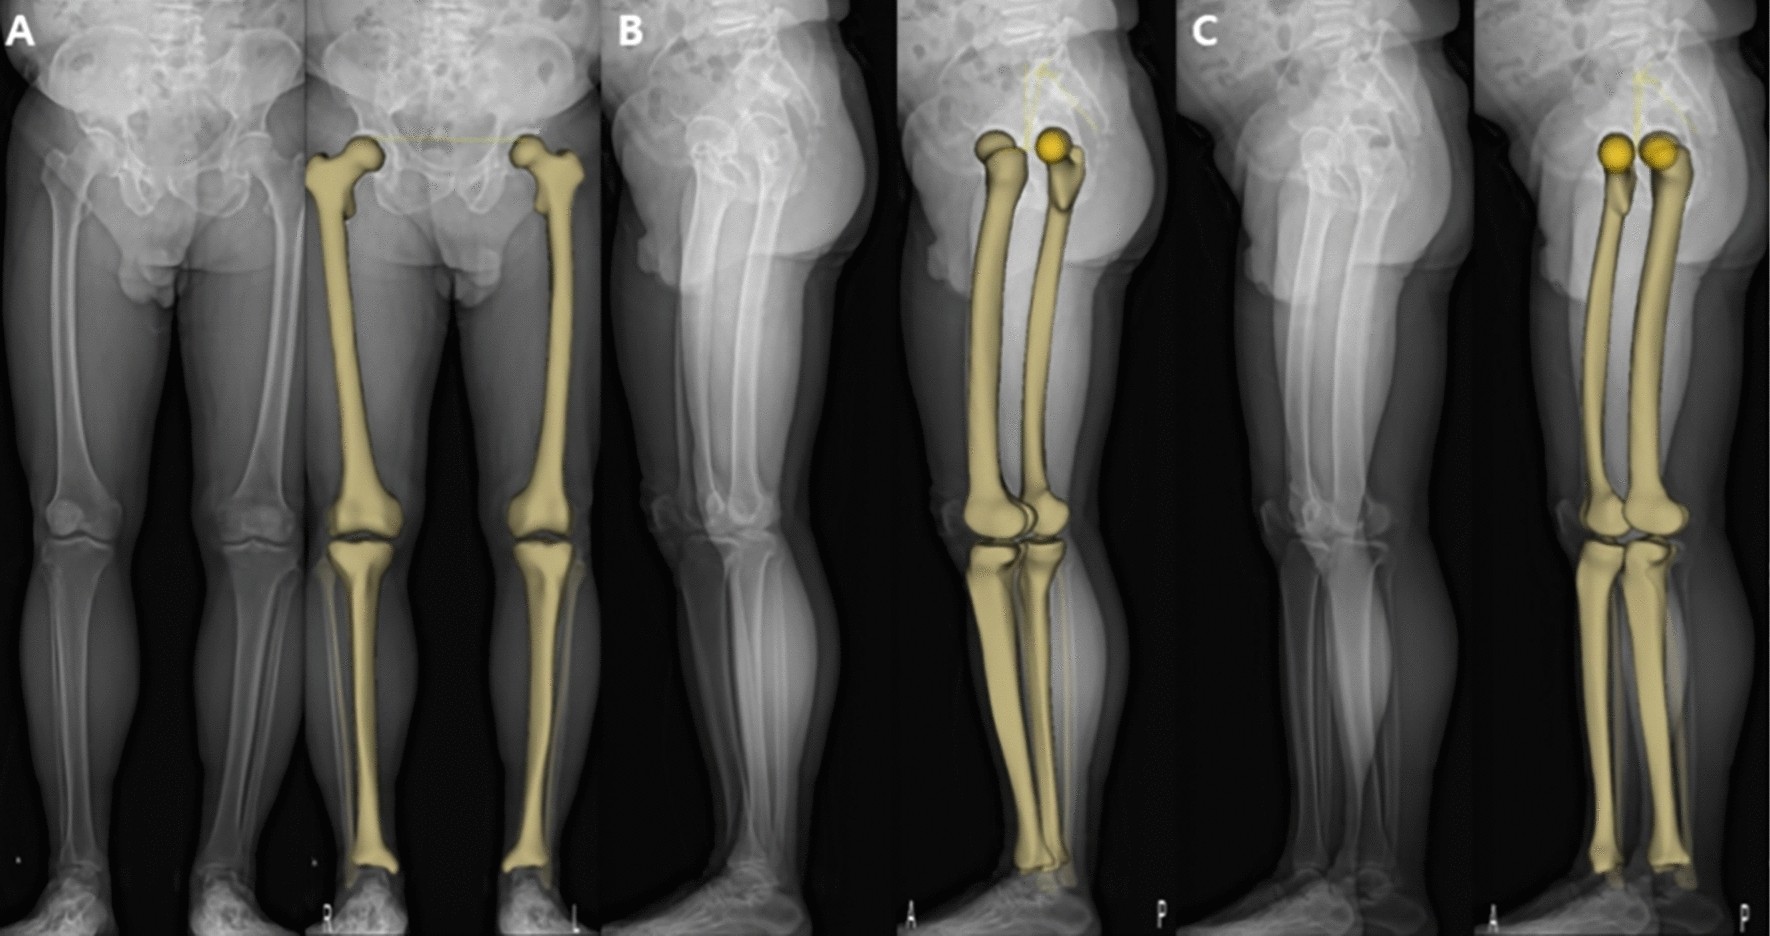

Figure 2

Three-dimensional (3D) model based on the EOS imaging system. Anteroposterior (A) and lateral radiographs (B and C) are acquired for 3D modeling. The 3D model is adapted to the osseous contours on radiographs.